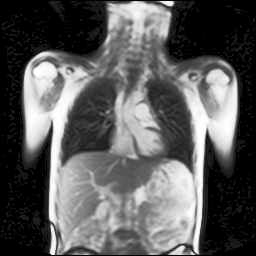

Refer to captionRefer to captionRefer to captionRefer to captionRefer to captionRefer to captionRefer to captionRefer to captionRefer to captionRefer to captionRefer to captionRefer to captionRefer to captionRefer to caption

Figure 5: Maximum inspiration (top row) and maximum expiration (bottom row) for different slice positions of one patient from back to front.

For a complete chest volume coverage, the lung is scanned at different slice positions as shown in Figure 5. At each slice position, a dynamic 2D+t image series with 140 images is acquired. For the further analysis of the image data, all images of one slice position need to be spatially aligned. We choose the image which is closest to the mean respiratory cycle as fixed image of the series. The other images of the series are then registered to this image. Our data set consists of 48 lung acquisitions of 42 different patients. Each lung scan contains between 7 and 14 slices. We used the data of 34 patients for the training set, 4 for the evaluation set, and 4 for the test set.